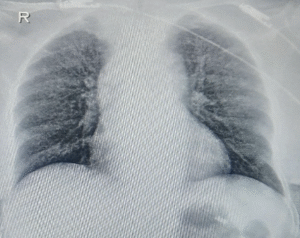

On magnetic resonance spectroscopy, lipid lactate peak was present. ELISA for IgG antibodies against cysticercosis was negative. Skiagrams of limbs and stool analysis showed no evidence of cysticercosis. Tuberculin skin test was positive. CSF analysis showed clear fluid with elevated monomorphic cells, hypoglycorrhachia and elevated protein. Adenosine deaminase (ADA) level was mildly raised. CBNAAT was positive for Mycobacterium tuberculosis without rifampicin resistance. Diagnosis of CNS TB was made on a microbiological basis with supportive radiological evidence, and first-line antitubercular therapy (ATT) with corticosteroids was started as per national guidelines. Chest xray was suggestive of miliary pattern (Figure 2).

Figure 2: The chest X-ray (poster anterior view) reveals a diffuse, bilateral, fine nodular pattern throughout both lung fields.